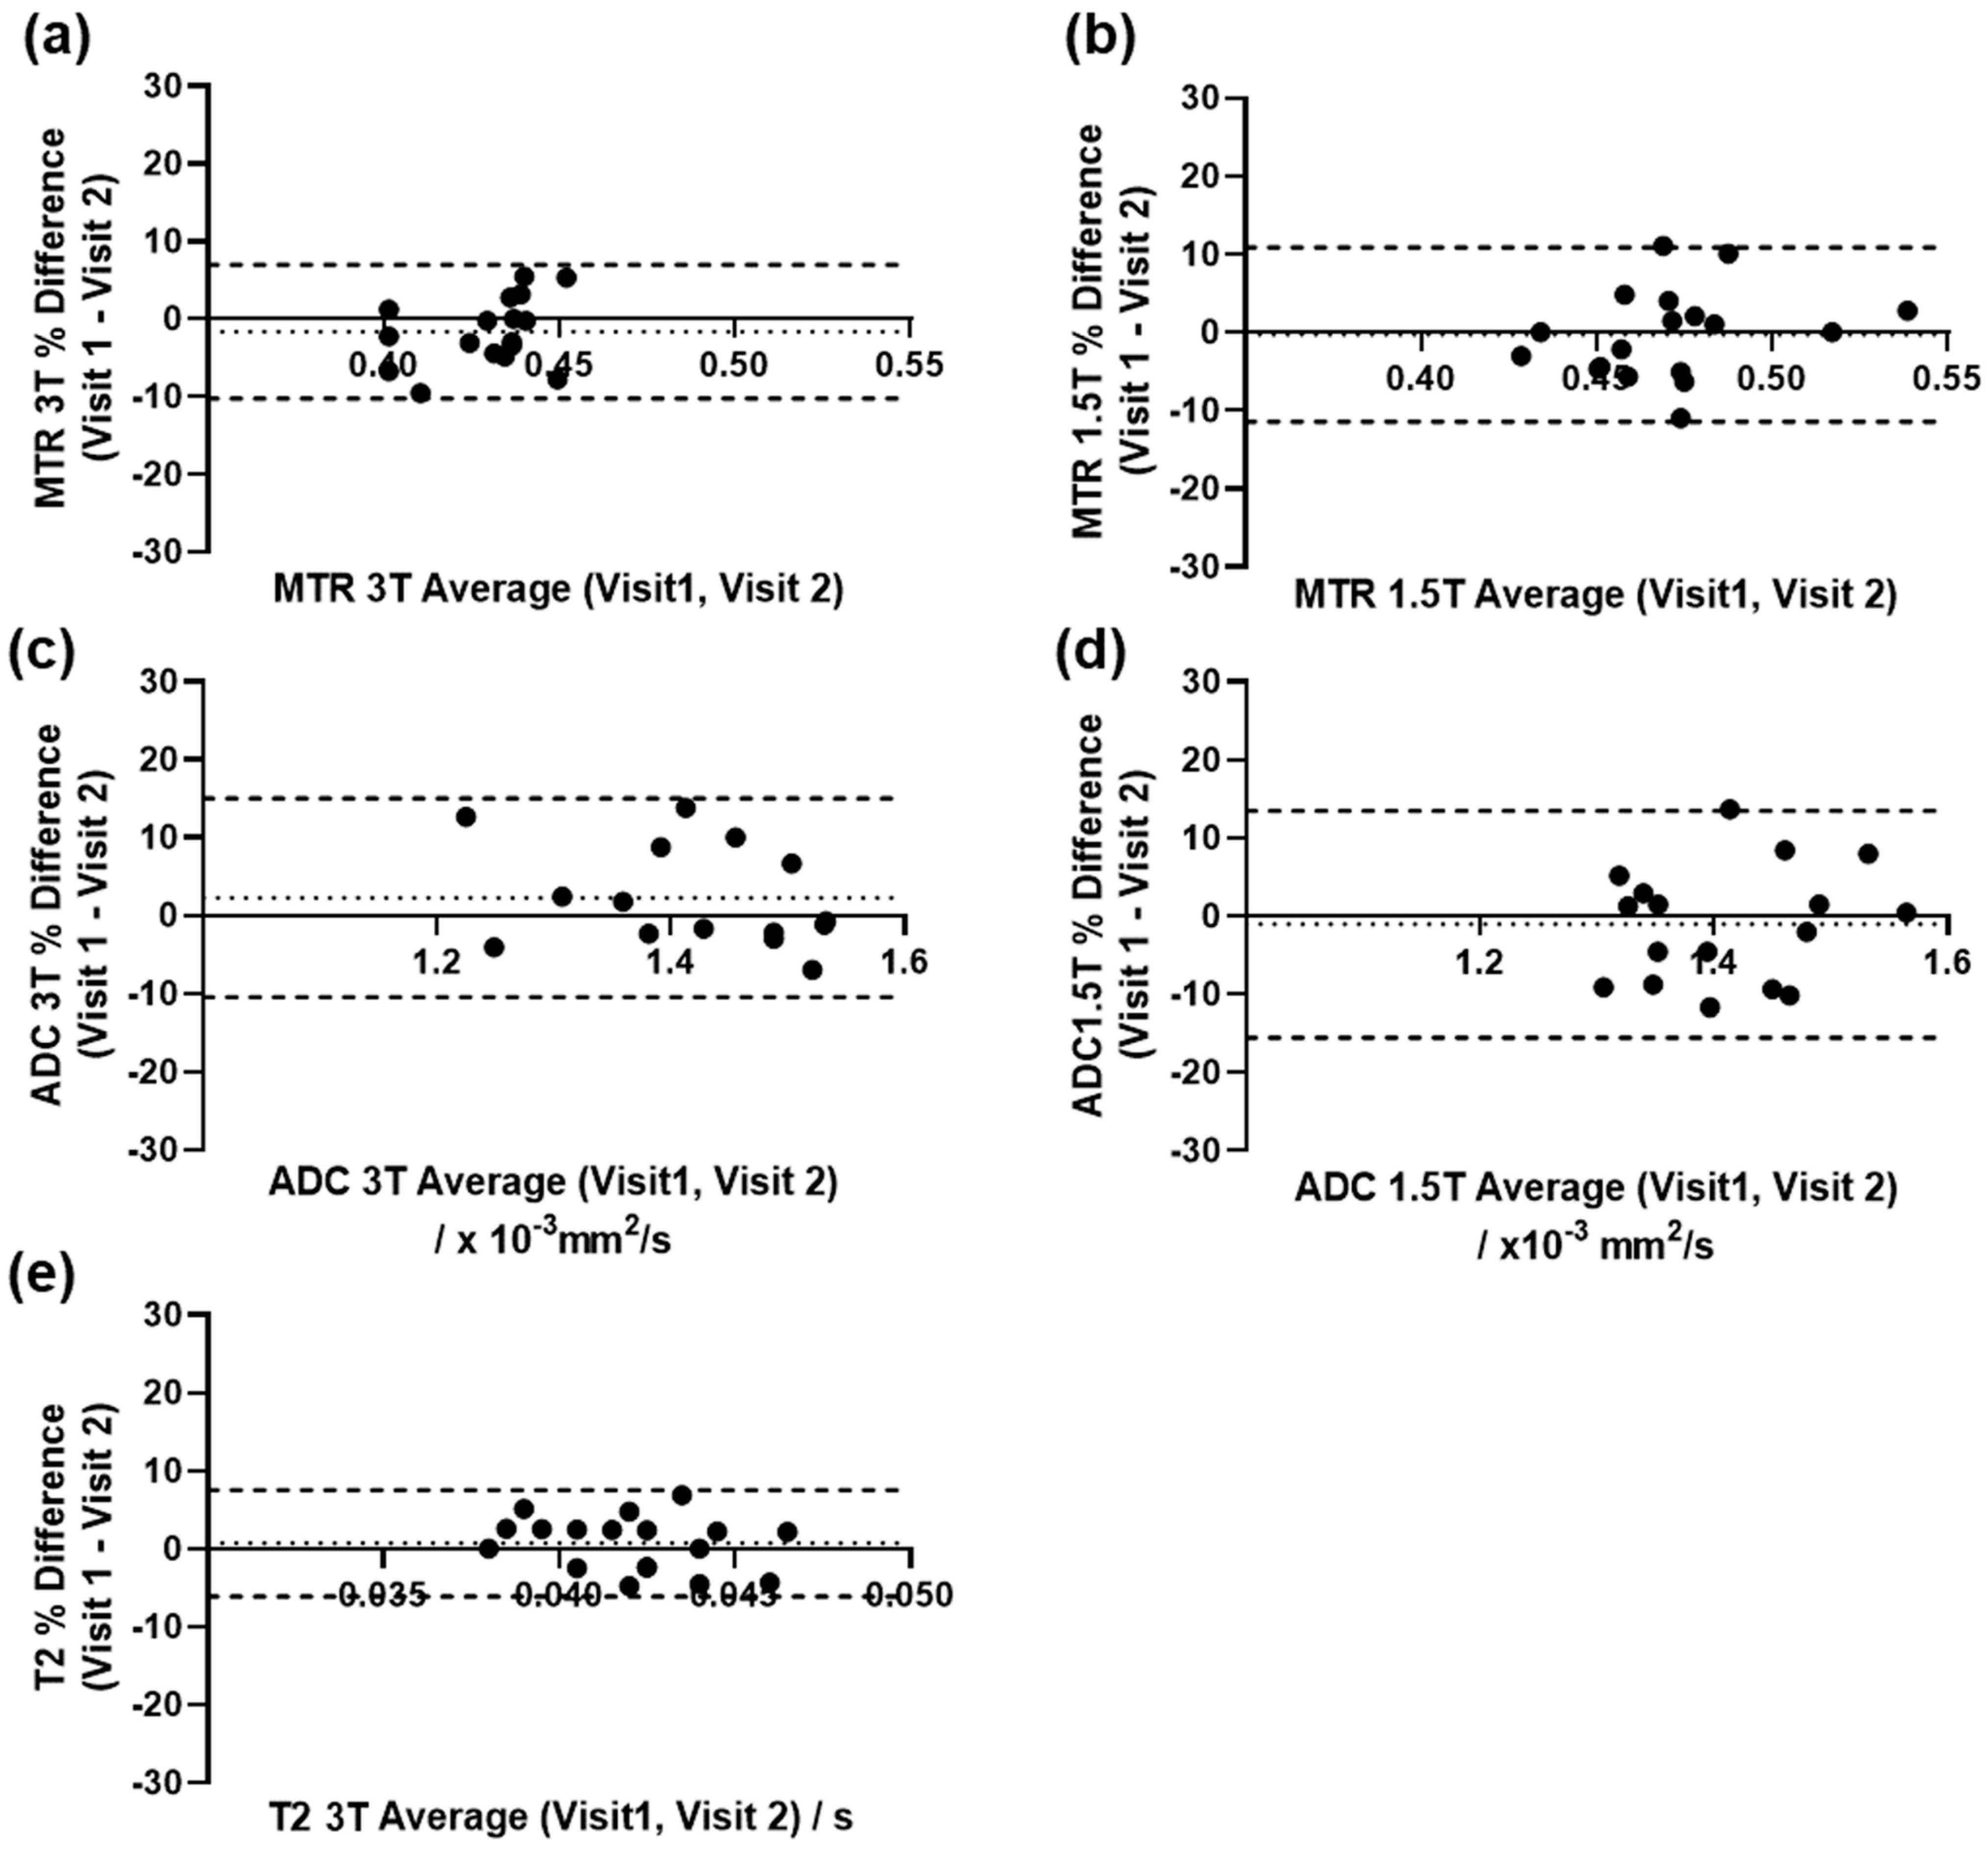

2.3.2. Repeatability of Quantitative Measurements

3.3. Repeatability of Quantitative Measurements